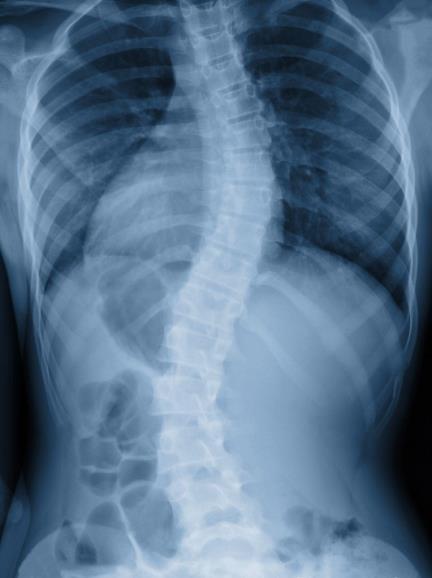

A escoliose é uma curvatura anormal da coluna para um dos lados que pode ser notada quando olhamos as costas. A coluna vertebral é alinhada, reta. Na escoliose, ela forma uma curvatura em “C” ou “S”.

Um dos sinais típicos da escoliose é a alteração da postura lateral, ou seja, um desvio na coluna que se mostra quando observamos a pessoa de frente ou de costas.

Além disso, pode ser possível notar um desalinhamento do quadril e dos ombros ou ainda a sensação de que uma perna é maior do que a outra.

O exame físico é parte importante no diagnóstico, pois irá avaliar sinais específicos de escoliose (inspeção, palpação, medições, exame neurológico e manobras especiais).

O médico especialista em coluna conseguirá atribuir o diagnóstico através de exames de observações posturais, ortopédicas e de exames de imagens como radiografias panorâmicas, ou outros exames, quando necessário.